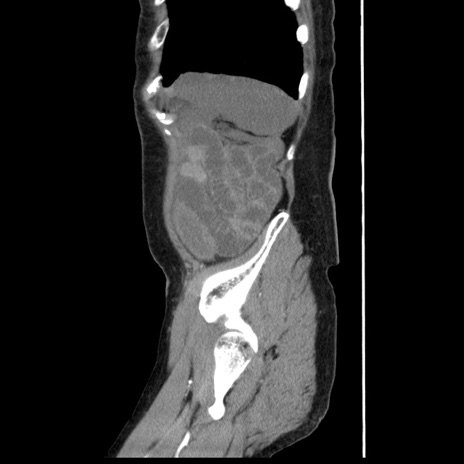

横断像

【症例】80歳代女性

【主訴】腹痛

【現病歴】8時間前から腹痛あり来院。

【既往歴】糖尿病、脂質異常症、子宮体癌にて子宮全摘術

【身体所見】意識清明・会話良好だが腹痛で苦悶様、全腹部にわたって反跳痛と圧痛あり

【データ】WBC 13600、CRP 0.14、LDH 224、CK 90